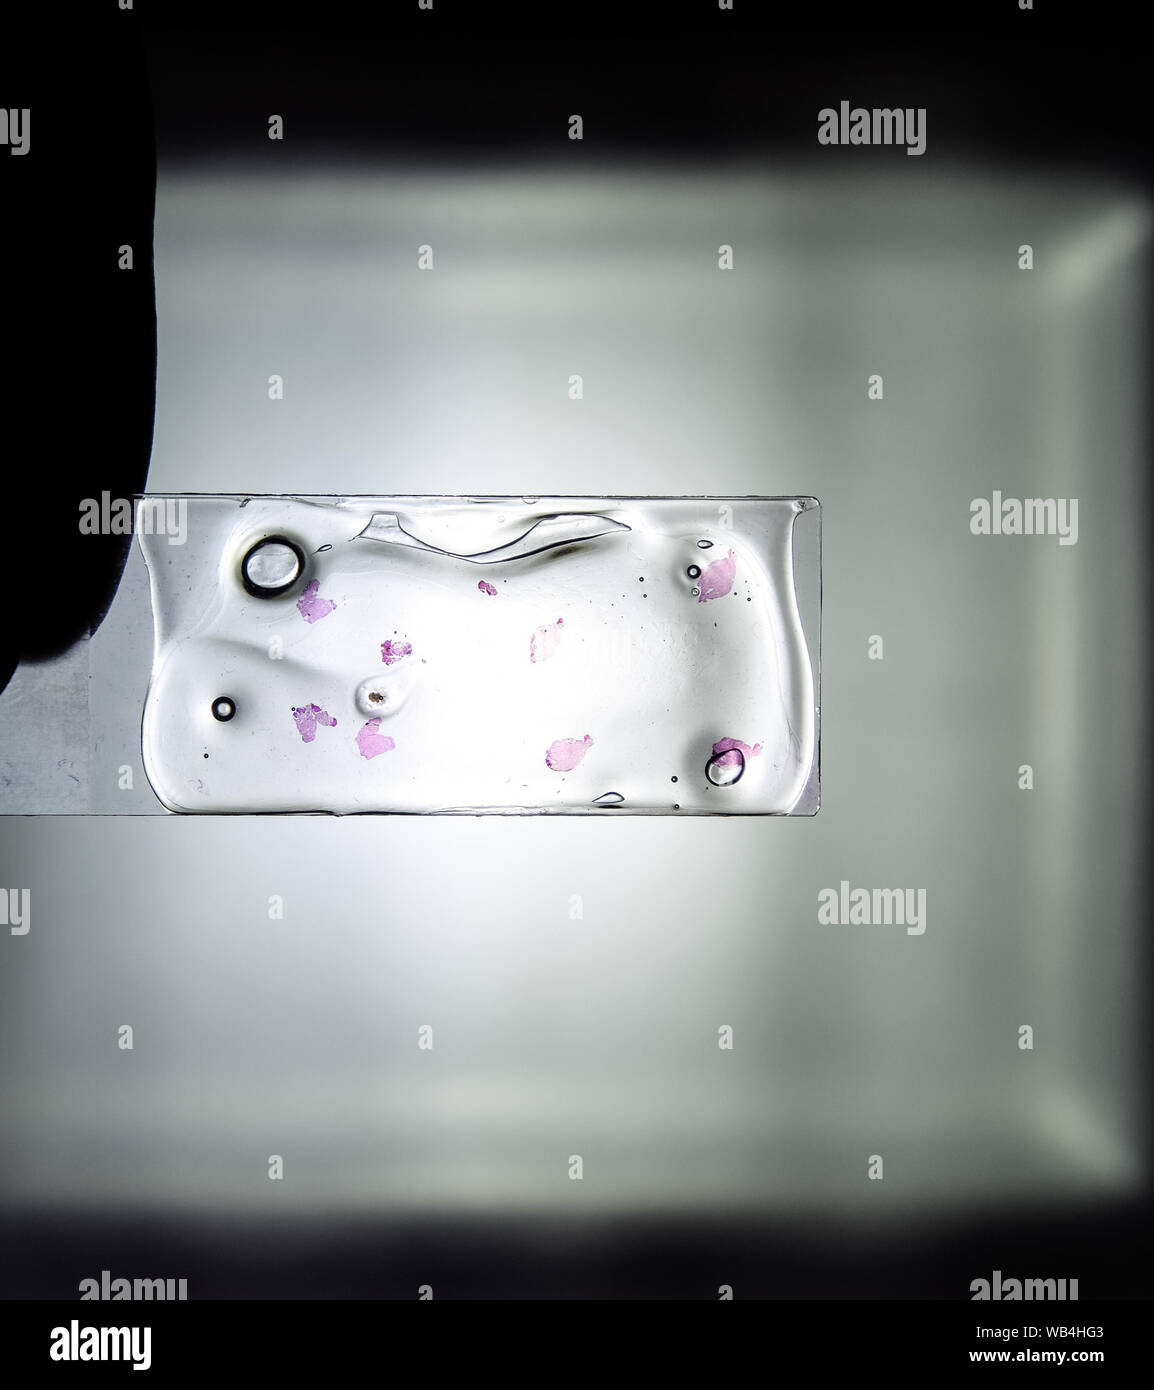

Bei der histologischen Untersuchung wird eine komplette Gewebeprobe begutachtet. Dieser Test wird durchgeführt, um die Struktur des Gewebes zu analysieren und zu sehen, ob es normal oder abnormal ist.(Bei histologischen Untersuchungen wird ein Gewebe untersucht, bei zytologischen Untersuchungen werden einzelne Zellen analysiert. Dort wird man feststellen, ob bereits Krebszellen im Polypen vorhanden waren und ob der Polyp vollständig entfernt wurde. Bei einer Laboruntersuchung bedeutet ein „positiver“ Befund, dass ein .Untersuchung von Gewebe und Zellen bedarf es einer umfassenden Beurteilung, Aufarbeitung und Asservierung der Präparate. Der Begriff Histologie umfasst die Wissenschaft und Lehre sowohl vom Feinbau als auch der Funktion der verschieden Körpergewebe.Diagnose Krebs: Untersuchungen und Methoden der Diagnostik. Bei dieser Entscheidung spielen auch Menge . In der Regel werden Materialien . Abhängig vom Befund des Pathologen kann . Von diesem Befund hängt ab, zu welchem Zeitpunkt die nächste Kontrolluntersuchung stattfinden sollte.Wenn zunächst der Verdacht auf Krebs besteht: Dann sind meist mehrere Untersuchungen notwendig: Damit lässt sich feststellen, ob es sich um eine gutartige Veränderung oder um eine Krebserkrankung handelt.